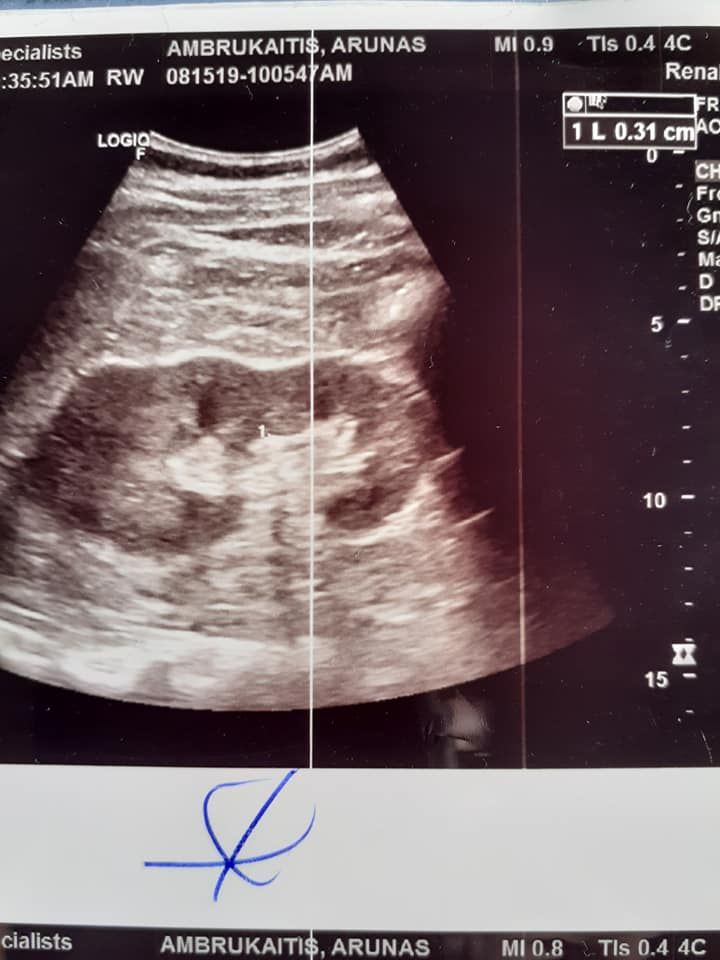

08/15 I was diagnosed with 3 mm stone in the L.kidney. 2 weeks latter ultrasound proved effect of healing with codes method.